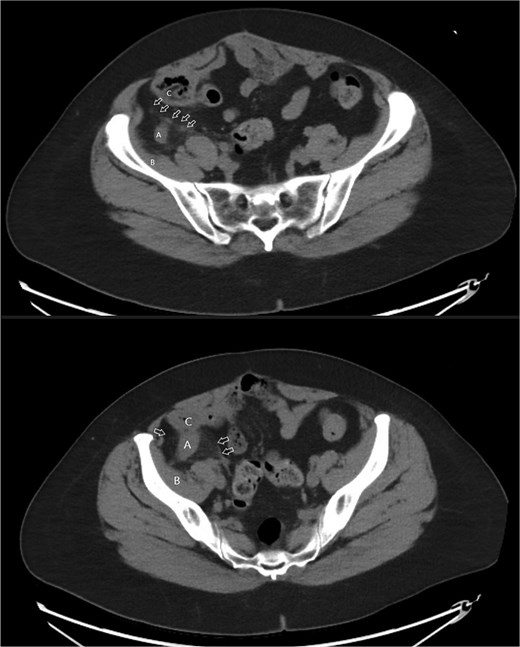

A 58-year-old female with a history of ovarian cancer, status post total abdominal hysterectomy, bilateral salpingo-oophorectomy, and omentectomy, presented with a 1-week history of right lower quadrant and right pelvic abdominal pain. Her labs were unremarkable. A CT scan of the abdomen and pelvis revealed a distended, fluid-filled appendix measuring 1.7 cm in diameter, with associated mesenteric infiltration and several small lymph nodes in the right lower quadrant, consistent with acute appendicitis (Fig. 1). The surgeon’s review of the scan was suspicious of retrocecal appendix (Fig. 2).

Axial images of CT scan with IV contrast showing appendix within retrocecal position in proximity within iliacus space. (A) Appendix; (B) iliacus muscle; (C) cecum.